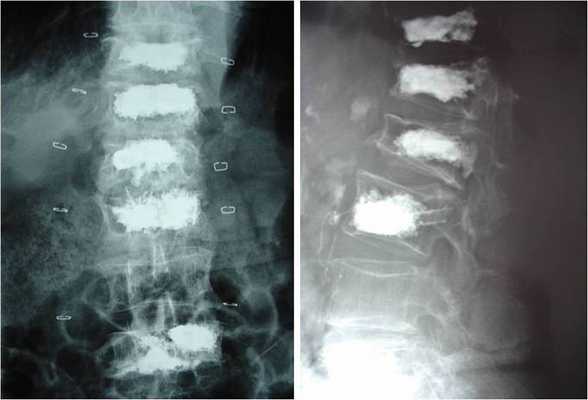

Хирургические вмешательства выполняют на поясничных и грудных отделах, преимущественно с целью устранения дефектов костной ткани по причине остеопороза. Рассмотрим все показания, итак, прохождение вертебропластики и кифопластики рекомендуется, если диагноз показал:

- на фоне остеопороза при снижении показателей высоты тела позвонка не больше чем на 70%, сопровождающегося болью на уровне поражения;

- остеокластические разрушения позвонков при множественной миеломе, остеолитических метастазах; тотальное и субтотальное поражение позвонка гемангиомой агрессивной формы;

- сагиттальная деформация позвоночника (кифоз), ставшая следствием коллапса тел позвонков на почве остеолиза/остеопороза (рекомендована кифопластика).

Слева кифо-, справа вертебропластика.